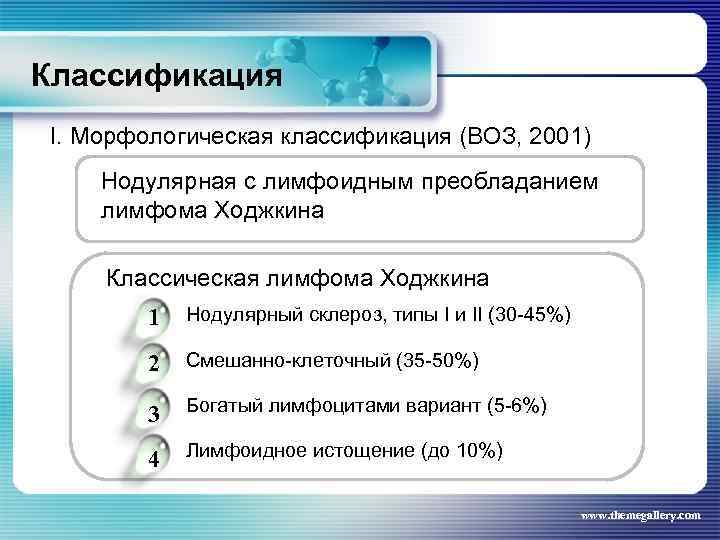

Классификация I. Морфологическая классификация (ВОЗ, 2001) Нодулярная с лимфоидным преобладанием лимфома Ходжкина Классическая лимфома Ходжкина 1 Нодулярный склероз, типы I и II (30 -45%) 2 Смешанно-клеточный (35 -50%) 3 Богатый лимфоцитами вариант (5 -6%) 4 Лимфоидное истощение (до 10%) www. themegallery. com

Классификация I. Морфологическая классификация (ВОЗ, 2001) Нодулярная с лимфоидным преобладанием лимфома Ходжкина Классическая лимфома Ходжкина 1 Нодулярный склероз, типы I и II (30 -45%) 2 Смешанно-клеточный (35 -50%) 3 Богатый лимфоцитами вариант (5 -6%) 4 Лимфоидное истощение (до 10%) www. themegallery. com